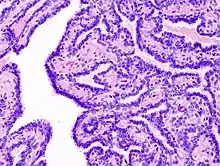

Histologia

.jpg.webp)

Tem por característica a proliferação do epitélio escamoso estratificado, arranjado em projeções semelhantes a dedos. Os coilócitos (células epiteliais alteradas pelo HPV) apresentam espaços perinucleares claros e núcleos muito corados. O tecido conjuntivo pode apresentar alterações inflamatórias em lesões sujeitas a traumatismos recorrentes.[5]